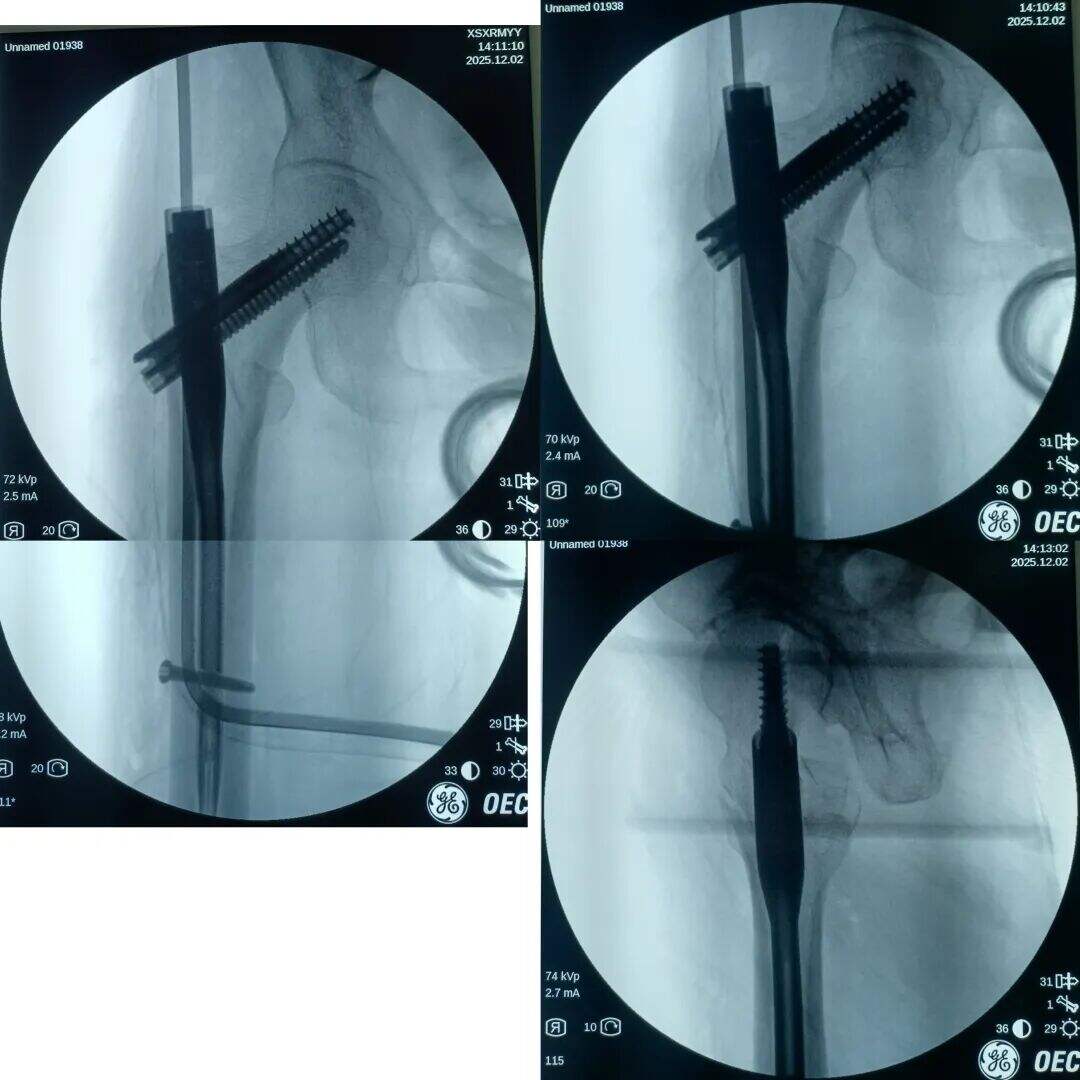

Postopek med operacijo:

Poskus zaprta zmanjšanja, vendar ni uspel. Več vlečne sile je uporabljeno, več je bilo premaknjen v višji del zaradi vlečenja iliopsoas mišice.

Narezen je bil 2 cm prednji mini-rez. Mesto zloma je bilo opazovano z prstom. Ugotovljeno je bilo, da je proksimalni fragment premaknjen navzgor, distalni fragment pa nazaj in zaklenjen. V mesto zloma je bil vstavljen klešča; pod vodstvom prsta v kombinaciji s kleščo so bili zaklenjeni fragmenti odklenjeni. Nato je bila klešča uporabljena za ohranitev kakovosti redukcije z medialno in lateralno kompresijo. Izvedena je bila običajna lokalizacija, vstavitev vodilne žice ter standardni kirurški postopek.

Medularni kanal je bil ozek. Nobenega razširjanja ni bilo izvedeno. Intramedularni klin s premerom 9 mm je bil vstavljen v tesen fit. Prilagoditev anteversije cefalomedularnega vijaka se je izkazala za težko.